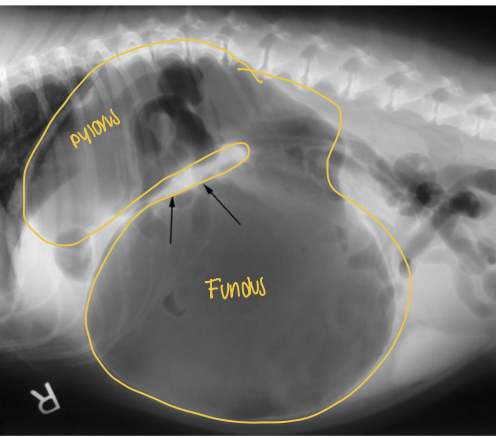

what does the radiograph show?

gastric volvulus displacing pylorus to dorsal left

displacement of pylorus from gastric voluvulus